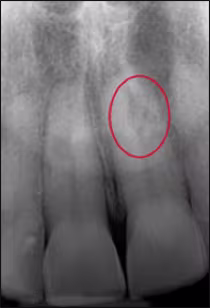

In the next case, Patient B presented to the dental office with a complaint about their front tooth. After taking the panoramic image (Figure 14), it was noted that tooth #9 had resorption on the root. The dentist then requested a periapical radiograph to evaluate the condition more closely (Figure 15). Upon review of the periapical image, it was confirmed that internal resorption was occurring in tooth #9 and the dentist was able to treat the condition accordingly.

Figure 15. Patient B: Part 2

Periapical image of Patient B, which confirmed internal resorption was occurring on tooth #9.